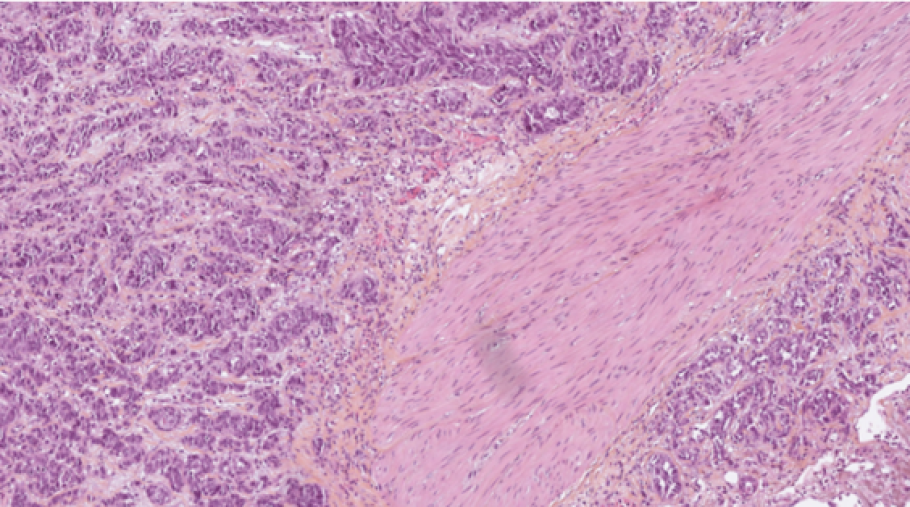

Des équipes du monde entier seront mises en concurrence pour développer le modèle d’intelligence artificielle (IA) le plus performant capable de prédire l’efficacité de l’immunothérapie chez les patients atteints d’un carcinome urothélial de la vessie. La compétition se basera sur l’analyse d’une base de données inédite d’environ 500 lames histologiques numérisées.

Une base de données unique de lames histologiques

Trois centres français participent à la constitution et l’annotation d’une base de données inédite d’environ 500 lames histologiques numérisées de carcinome urothélial de la vessie.